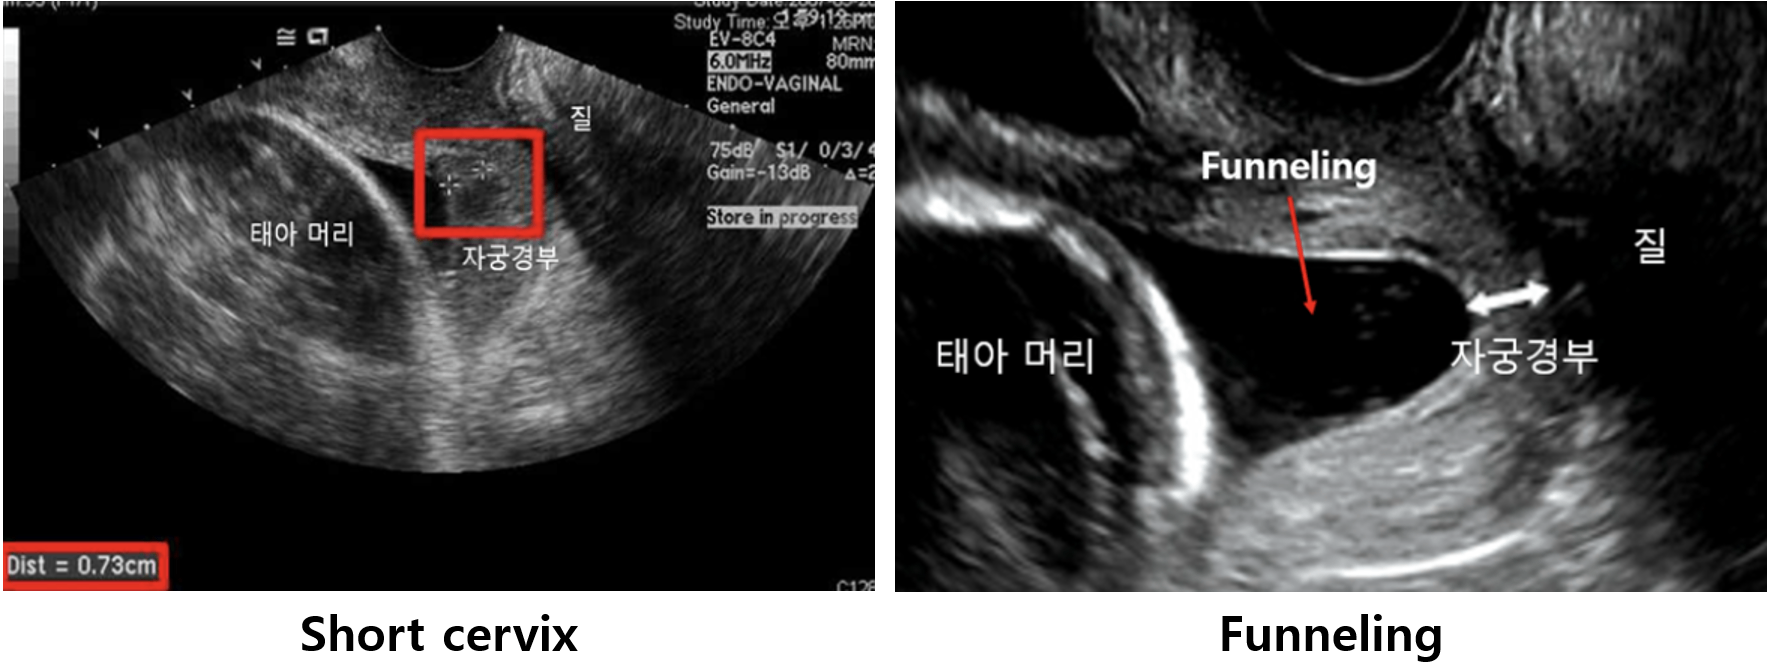

2. 짧은 자궁경부(short cervix)

(1) 조산의 가능성을 예측할 수 있는 주요 소견

(2) 정의: US상 자궁경부 길이 2.5 cm

3) 자궁경부무력증(cervical insufficiency)

(1) 정의: 임신 2분기에 통증 없이 자궁경부가 개대되는 현상

(2) 검사소견

짧은 자궁경부 (길이 ≤ 2.5 cm)

Funneling: 자궁경부의 external os는 닫혀있으나 internal os가 열려 양막이 내려온 깔때기 모양의 소견